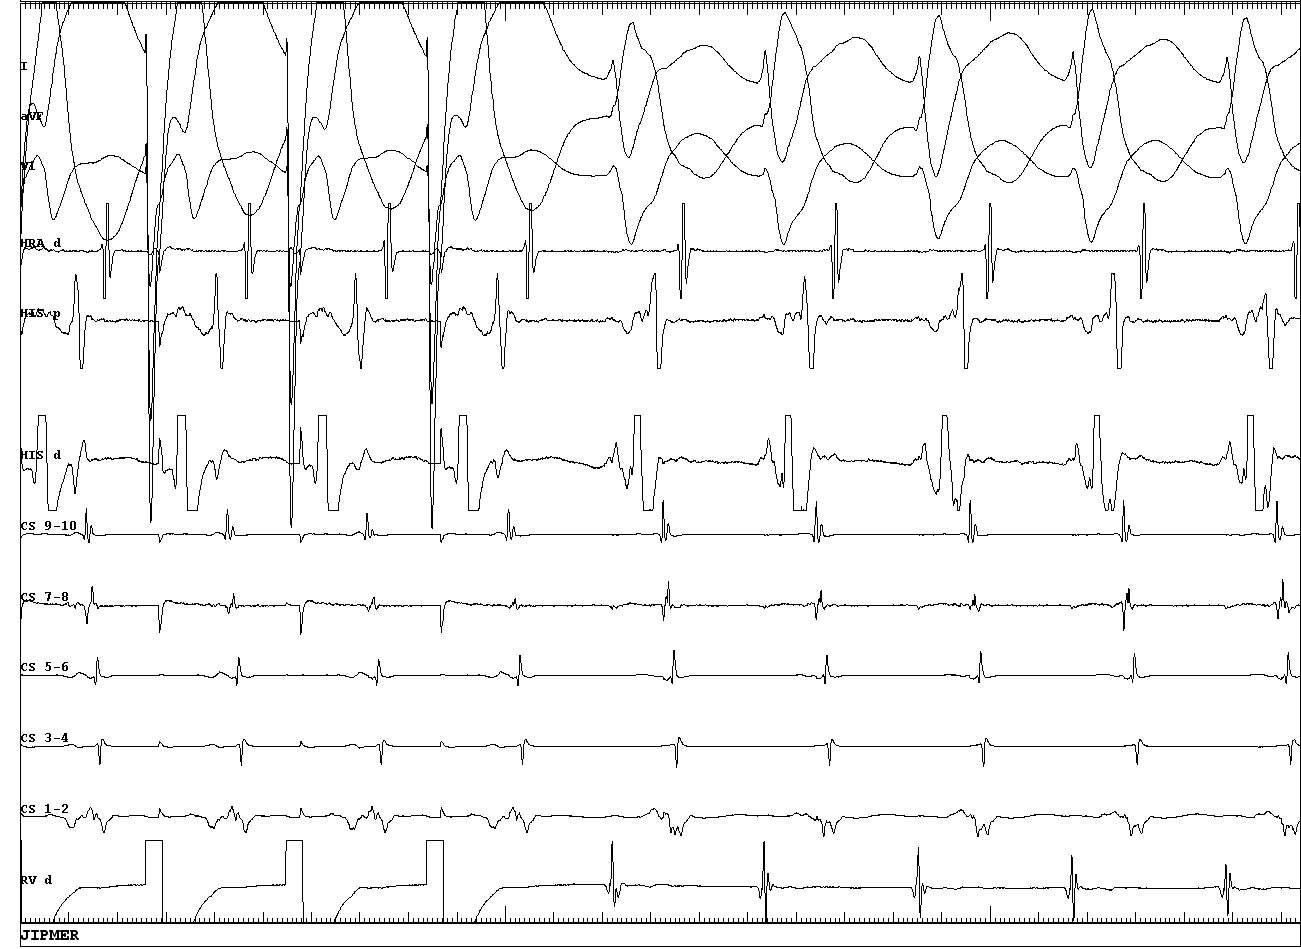

Antegrade conduction is decremental

02_decremental_antegrade.JPG